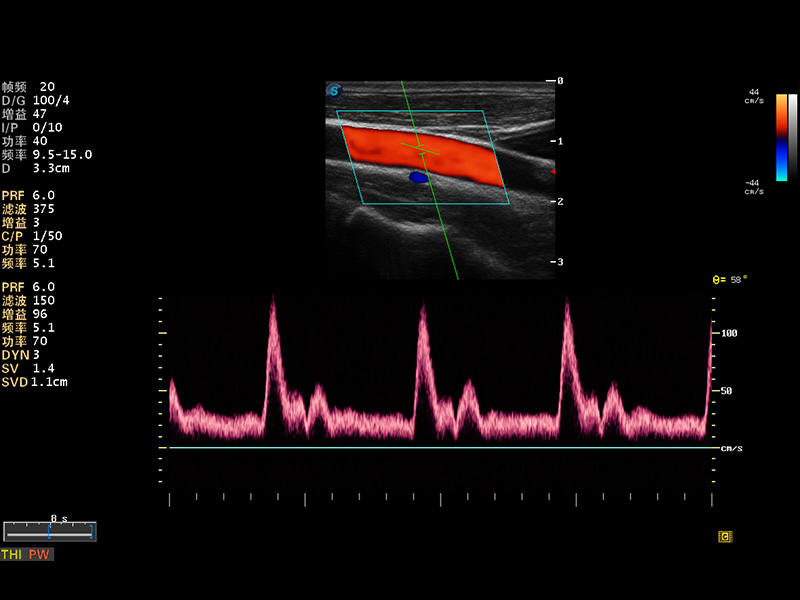

S8 EXP便携式彩色多普勒超声诊断仪是milan米兰研发的高端全身应用型便携彩超。高通道的VIS平台融合可视化(Visual)、智能化(Intelligent)和人性化(Smart)的特点,配以milan米兰自主研发生产的探头大家族,使您能够快速、准确的获得病人信息,提高工作效率的同时减轻疲劳。

多波束形成器

μ-Scan微米成像